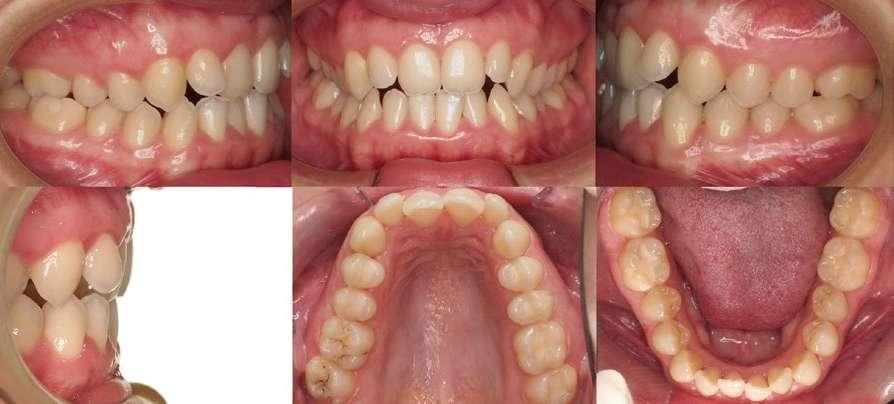

2.- Análisis intraoral (Fig. 3)

 Relación molar y canina de clase I.

 Compresión dentoalveolar en ambas arcadas con leve apiñamiento.

 Retroinclinación de los incisivos superiores e inferiores.

 Mordida borde a borde (resalte disminuido).

 Tendencia a mordida abierta.

 Línea media superior centrada con respecto a la línea media facial.

 Desviación de la línea media inferior 1 mm hacia la derecha respecto a la línea media facial.

Fig. 3: Fotografías intraorales iniciales.